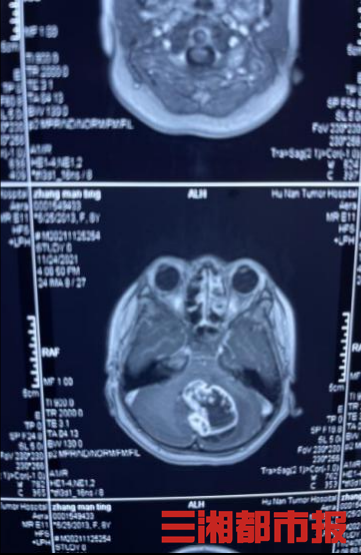

11月底,张先生的9岁女儿慕慕(化名)突然出现头痛、恶心、走路不稳等症状。连日来,这样的症状还不断加重,当地医院头部磁共振检查显示小脑蚓部占位性病变,考虑恶性髓母细胞瘤。

该科室杨杰教授及团队立刻给慕慕安排住院及术前检查,并给其父母下达了病危通知书,同时告知患儿父母亲相关手术事宜及风险。患者父母心情忐忑,商议后坚持手术治疗。杨杰教授率领医护团队,连夜加班讨论、分析病情,为其制定细致的手术方案及术后措施,决定于次日急诊行开颅探查+小脑蚓部占位性病变切除术。

随后,由主任医师杨杰主刀,副主任医师陈帅、章凯协助,手术团队成功为患儿实施开颅手术,完整切除肿瘤。从接诊到手术完成,医护团队历经24小时,成功将患儿从生死边缘拉了回来。

杨杰教授介绍,该患儿的术中快速病理显示为小脑蚓部恶性肿瘤,后续还应尽早进行基因检测,接受放化疗。